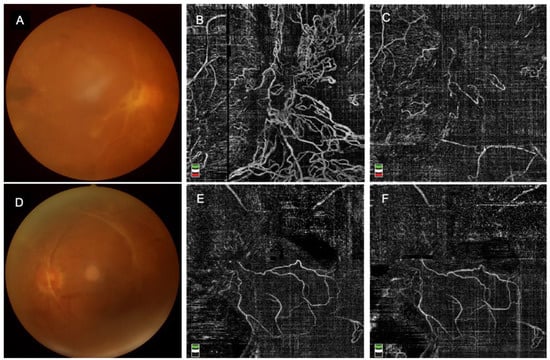

3.3. Fundus Images (Figure 2)

Before PPV surgery, fundus images were taken for each participant to present the fundus condition. As shown in Figure 2, after intravitreal conbercept injection, the choroidal neovascularization(CNV) decreased significantly in the IVC group, while in the No-IVC group, it had no significant change. Anti-VEGF treatment immediately reduces CNV and thus inhibits proliferation.

Figure 2.

Images of the representative cases with and without IVC, (A). Fundus photograph before IVC, (B). OCTA image before IVC, (C). OCTA image after IVC, (D). Fundus photograph in the No-IVC group, (E,F). In the No-IVC group, OCTA images scanned at the same time as patients in the IVC group.